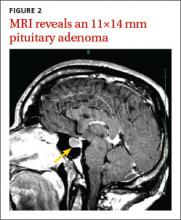

Magnetic resonance imaging (MRI) of our patient’s brain revealed a pituitary adenoma (FIGURE 2). Based on that and the patient’s elevated GH and IGF-1 levels, we diagnosed acromegaly due to a pituitary adenoma.